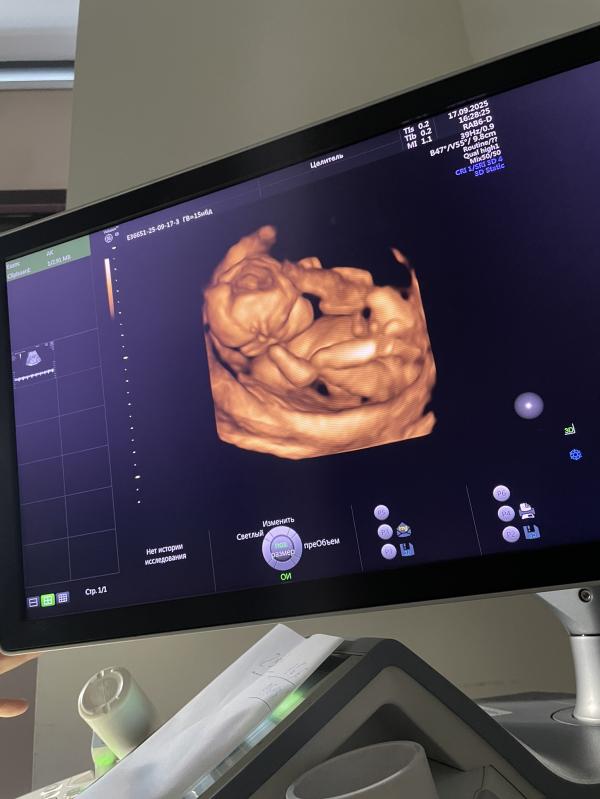

Вторая беременность: эмоции УЗИ и ожидание 2 скрининга

post image 2

сколько я умилялась на узи, такие эмоции испытала вновь…

маленький малыш💖

не на секунду этот малыш не остановился, то ножками то ручками))

из-за тонуса бедный лежит согнув коленки